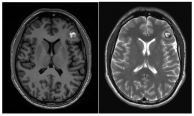

Figure 2.

(a). Axial and coronal T2-weighted MRI of a 54-year-old patient affected by an incidentally discovered familial form of CM. Multiple asymptomatic CMs were observed supratentorially, infratentorially, and at the brainstem. (b). Sagittal T1-weighted and axial T2-weighted MRI showing a concomitant symptomatic parieto-occipital meningioma, which required surgery (red arrow). (c). Pre- and postoperative CT scan with contrast showing total removal of the meningioma (red arrow) and multiple hyperdense lesions corresponding to CMs.